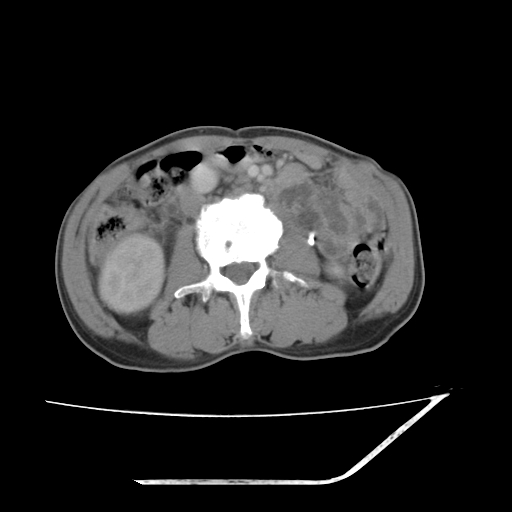

平扫

考虑右肾盂癌,肾动脉受侵,右肾功能减退,右肾盂输尿管积水,管壁增厚,考虑种植转移,应该把下面扫完的

支持右侧肾盂癌伴肾静脉瘤栓形成可能性大,右肾结石.肝右叶后段低密度影,不除外转移.

考虑右肾盂癌,肾动脉受侵,右肾功能减退,右肾盂输尿管积水,管壁增厚,考虑种植转移  支持

右肾盂旁ca并肾静脉瘤栓形成/肾功能降低。

右肾结石。

右肾盂癌,肾动脉受侵,右肾盂输尿管积水,管壁增厚,考虑种植转移

右肾盂移行细胞癌并右输尿管中段转移.肾积水.

支持 右侧肾盂癌伴肾静脉瘤栓形成可能性大,右肾结石;肝右叶后段低密度影,不除外转移。

1.右侧肾盂癌伴肾盂积水。

2.肾脏功能减退,原因有:(1)肾动脉受侵。(2)肾静脉受侵(3)肾积水,等。本例,肾动脉显影较好,但受压明显;肾静脉无明显显示,受压或静脉癌栓,下腔静脉腔内未见明显充盈缺损。

3.右侧上段输尿管扩张,原因:(1)积水所致;(2)种植。